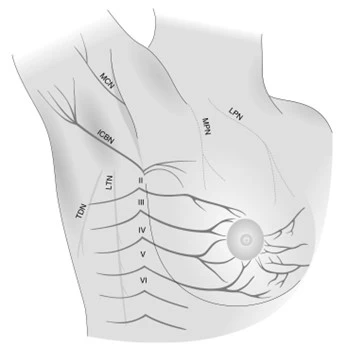

저는 환자분께 CI 주사치료를 권해드렸어요.

CI(C-arm Intervention) 주사치료는 C-arm이라는 영상장비를 보면서

정확하게 문제 부위에 약물을 주입하는 치료예요.

신경 주변의 염증을 가라앉히고 압박을 줄여주는 거죠."